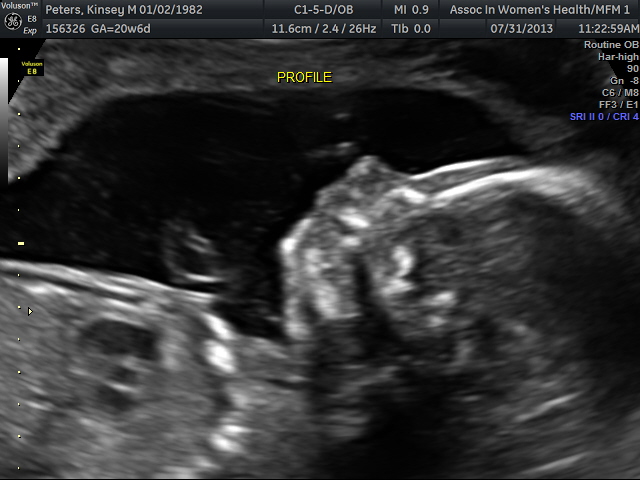

I am 20 weeks. My due date is December 12th. We are not going to find out the sex, just like we did with Henry.  I was nauseous the first trimester, but have felt great ever since.  This pregnancy is very similar to my pregnancy with Henry.  I don't have as much heartburn, which is nice.  The kids will be 18 months apart.  Yes, this was planned.  The kids will share a room until we move, at some point in the future.  I'm still working out with my mom's group and I'm pretty sure that is why I feel so great and have enough energy to run after a 14 month old.  According to our sonogram today, everything looks picture perfect.  This one likes to wave just like big brother.